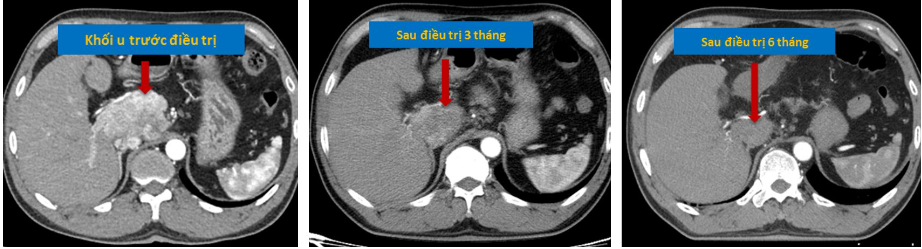

| Khối u gan đáp ứng hoàn toàn sau xạ trị SBRT - Nguồn: Khoa Xạ trị - Xạ phẫu, Bệnh viện Trung ương Quân đội 108 |

Các nghiên cứu điều trị SBRT ung thư gan giai đoạn sớm có tỉ lệ kiểm soát tại chỗ 2 năm từ 75% đến 95%, đây là kết quả đầy hứa hẹn gần tương đương như phẫu thuật. Kết quả các nghiên cứu so sánh còn cho thấy xạ trị SBRT có tỉ lệ kiểm soát tại chỗ tương đương với RFA, thậm chí tốt hơn RFA với khối u gan trên 2cm.

Với ưu điểm là phương pháp điều trị không can thiệp với độ an toàn cao, SBRT là lựa chọn điều trị thay thế đối với bệnh nhân ung thư gan giai đoạn sớm không có chỉ định phẫu thuật (bệnh nhân cao tuổi, có nhiều bệnh kết hợp, không có nguyện vọng phẫu thuật) hoặc vị trí không thuận lợi cho RFA. Vì vậy, SBRT sẽ là vũ khí mới mang lại niềm hy vọng cho bệnh nhân ung thư gan giai đoạn sớm.